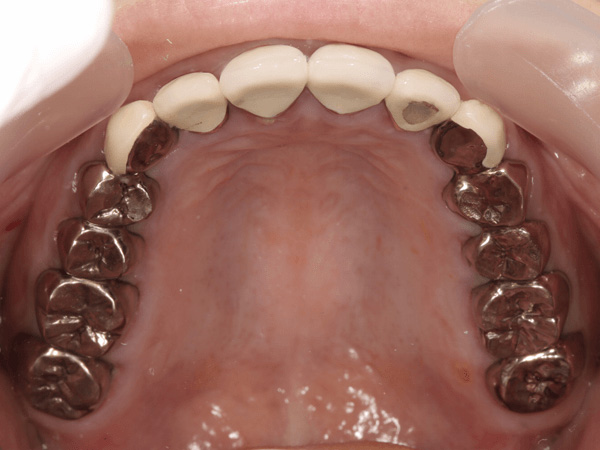

盲点であるのは、過去にむし歯治療をした歯です。一見キレイに銀歯が入っているように見えます。しかも銀歯で全周覆われているので、むし歯菌が歯に侵入しないように思えますが、実際はどうでしょうか?

金属のかぶせを外すとこのようにむし歯でボロボロになってしまっているのがわかります。なぜこのようになってしまったかというと、歯と金属のかぶせ物の間に隙間があったからです。むし歯菌は目に見えないほど小さく、むし歯菌の侵入を防ぐには、精度の高いかぶせ物を作る必要があります。